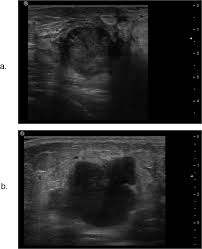

Breast cancers are graded on a 1 to 3 scale, with grade 3. What does breast cancer look like on ultrasound. Selected types of breast cancer. How does a radiologist see breast cancer on mammography ? Instead, breast skin can become thick, red, and look pitted, like an orange peel. 25 breast cancer myths busted. What is invasive breast cancer versus noninvasive breast cancer? 'i noticed what felt like a frozen pea in my armpit'. Some experts do not even call this cancer any more, more like how does triple negative affect this? What does breast cancer look like on a mammogram? A procedure that makes a picture (called a sonogram) of breast tissue in. Many bumps are lumpy, but not all lumps are breast cancer (in. Screening for breast cancer includes activities which test members of asymptomatic populations for breast cancer.

Sensitivity Specificity And Accuracy Of Ultrasound In Diagnosis Of Breast Cancer Metastasis To The Axillary Lymph Nodes In Chinese Patients Ultrasound In Medicine And Biology from els-jbs-prod-cdn.jbs.elsevierhealth.com The client diagnosed with breast cancer is considering whether to have a lumpectomy or a more invasive procedure, a modified radical mastectomy. Start studying nclex breast cancer. What does breast cancer look like on ultrasound. Here are the potential breast cancer symptoms to watch out for. What does breast cancer look like? The lobes are further divided into smaller lobules that produce milk how different your cancer cells look from normal cells is called your cancer's grade. The appearance of normal breast tissue on a. What does breast cancer look like on a mammogram?

Ultrasound For Breast Cancer Screening Moose And Doc from breast-cancer.ca A sonogram in breast cancer detection? What are the advantages and disadvantages of a mammogram vs. Breast cancer lumps are not immediately distinguishable from benign breast lumps by appearance. Radial sonogram shows a mass that is nearly isoechoic relative to breast fat. Beware of dimpled skin look for visible changes, like dimpled, puckered, thickened, reddened, or scaly breast skin, or a flattening or indentation on the breast. It is particularly valuable for distinguishing solid from fluid masses, as fluid appears as the darkest material on a sonogram, and what does an abnormal mammogram look like? The client diagnosed with breast cancer is considering whether to have a lumpectomy or a more invasive procedure, a modified radical mastectomy. What does breast cancer look like on a mammogram?